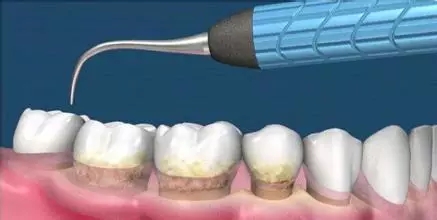

一、基礎治療

這是牙周病常規(guī)的治療方法,清除或控制臨床炎癥和致病因素,去除病因,消除炎癥。包括口腔衛(wèi)生宣教、充填齲洞、口腔潔治刮治、牙體牙髓治療、咬合調(diào)整、去除不良修復體、藥物治療(輔助手段,局部用藥效果好)、拔除治療效果不佳的牙周病患牙等。